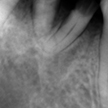

2. 初診時右下6番X線デンタル

初診時の主訴であった右下6番の歯冠が脱離した部位のX線デンタルです。患者様は銀歯が脱離してしばらく放置したとのことで、痛みもないので又歯冠をつければ良い位に考えていた様子でした。歯根吸収の状況より当時22歳とのことで、相当若年時に抜髄されたのが想像できます。考えてみれば6歳に萌出して15年で抜歯となった訳です。上顎8番の同部への移植も考慮しましたが断念しました。